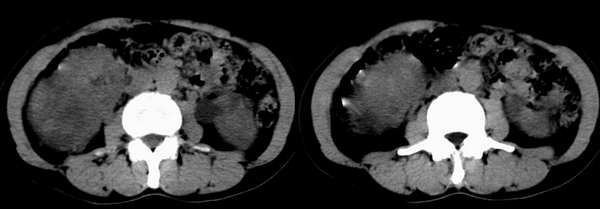

增强注药2小时后再次扫描

右肾体积增大,形态失常,其内可见多发低密度影,增强后动脉期病灶实质明显强化,低密度区未见强化,静脉期病灶呈等密度,考虑右肾癌,左肾多发囊肿,多囊胰

右肾内见不均匀强化软组织密度,考虑双侧多囊肾,多囊姨,右肾癌.

右肾癌  左多囊肾 胰腺(胰头周围淋巴结肿大)胰管扩张